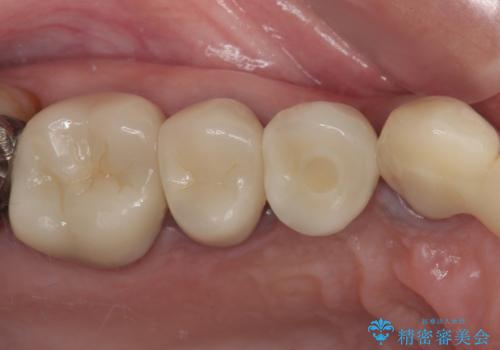

ブリッジのぐらつき インプラントを用いた奥歯の噛み合わせの再構築

歯ブラシのしやすい環境を整えるインプラント治療